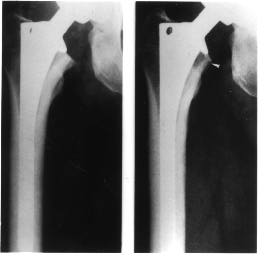

Many current joint replacement components are implanted without the use of bone cement. Porous surface treatments allow bone tissue to grow into the prostheses in order to provide stable long-term fixation. One area of concern for these joint replacements is relative motion (micromotion) between the prosthesis and the bone in the immediate post-operative period. If too much micromotion is produced when the patient uses the joint, the bone will not grow into the prosthesis. Instead of stable fixation, a fibrous (scar-like) tissue may develop which can lead to pain and eventual failure of the procedure. A second area of concern is long-term bone adaptation around the prostheses. When a natural joint is replaced with artificial components, the way the remaining bone supports the loads generated during daily activities is changed. Bone hypertrophies with increased loading and atrophies under decreased loading. Joint replacements generally result in reduced loading of the bone adjacent to the joint. This can lead to excessive loss of bony support for the prosthesis and subsequent prosthesis loosening (Figure 1).

to receive  figure click here Figure 1. X-rays of a femoral prosthesis. Compare the bone immediately after surgery (left) and after the prosthesis has induced bone loss (right).